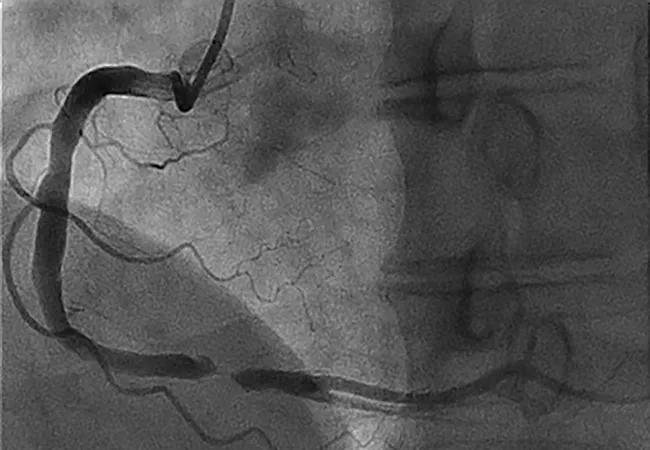

Antegrade Approach for Coronary CTO: Tapered-Tip, Low-Force Guidewires Deliver Good Results

An initial antegrade wiring escalation approach for crossing coronary chronic total occlusion (CTO) lesions using a new guidewire technology facilitates efficiency and success with excellent safety. So concludes a study recently published in the Journal of Invasive Cardiology (2020;32[5]:161-168) involving use of the guidewires for 164 consecutive CTO lesions treated at Cleveland Clinic.

The study assessed a guidewire type novel to the United States — polymer-jacketed, tapered-tip, low-force guidewires with composite-core, dual-coil design. The research was investigator-initiated and involved no formal industry funding.

For coronary CTOs, advanced crossing strategies associated with a higher risk of complication are often selected as alternatives to an antegrade strategy because of inadequate wire technology. But with the availability of new guidewires with technological advances (composite-core, dual-coil design with polymer-jacketed and tapered tips), both the Euro and Asia-Pacific CTO Clubs favor an antegrade-first strategy.